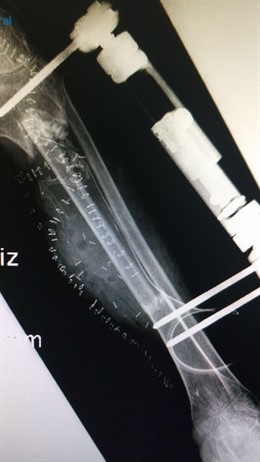

Radiografía de trasplante

JUNTA DE ANDALUCÍA

Profesionales del Hospital Regional de Málaga han realizado un trasplante de peroné a un paciente cuya única alternativa, tras ser sometido a más de una decena de intervenciones quirúrgicas, era la amputación de la pierna a consecuencia de una fractura abierta y atrición de partes blandas. Por su exposición al exterior esta se infectó ocasionando la pérdida progresiva de hueso por la osteomielitis secundaria.

El paciente, natural de Argelia, había sido sometido a técnicas de reconstrucción de la tibia con aporte de hueso no vascularizado en su país y, pese a los intentos de los distintos profesionales que lo habían tratado hasta la fecha, no se había conseguido que se formara hueso sano para producir la unión de la fractura.

Por ello, ante esta situación, los cirujanos de Traumatología y Cirugía Ortopédica del centro sanitario tuvieron que extirpar al paciente más de diez centímetros de hueso infectado, al que colocaron un fijador externo y trataron la infección sin poder reconstruir el defecto tibial dada la situación clínica del paciente, según han explicado desde la Junta a través de un comunicado.

En este caso, el hueso extraído fue una parte del peroné de la pierna derecha, sana, del paciente, de 18 años, para colocarlo en el lugar de la tibia extirpada.

"Este trasplante, novedoso en el caso de miembros inferiores, es de mayor complejidad por los trabajos realizados previamente sobre la tibia izquierda, la gran cantidad de fibrosis y por tratarse de un caso límite, puesto que si no se lograba la reconstrucción ósea la única solución era la amputación del miembro inferior izquierdo por encima de la rodilla", ha explicado.